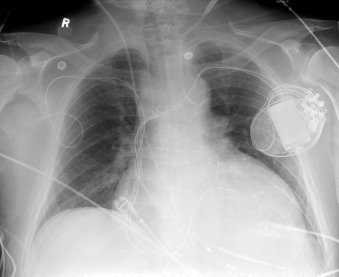

Chest radiography has a standard role to assess for the position of central venous lines and pulmonary artery catheters following their insertion.

Some postinsertion complications can be identified or excluded by chest radiography.

Determining malposition of catheters and tubes constitutes a forte of chest radiography and is mandatory following their insertion and repositioning.

Central Venous Lines ( Figs. 22-1 to 22-13 )

To avoid mechanical irritation (from the catheter tip) and chemical irritation (from infusate) of the right atrium, the catheter tip of a central venous line should be further than the junction of the internal jugular vein and subclavian veins (near the level of the first thoracic rib). In addition, the tip should not be further in than the junction of the superior vena cava and right atrium. Central venous catheters that are intended to record central venous pressure should lie distal to the last venous valves (in the subclavian and internal jugular veins, 2.5 cm proximal to the beginning of the brachiocephalic vein) and before the right atrium. The ideal position of the tip of a peripherally inserted central catheter (PICC) line is in the distal superior vena cava.